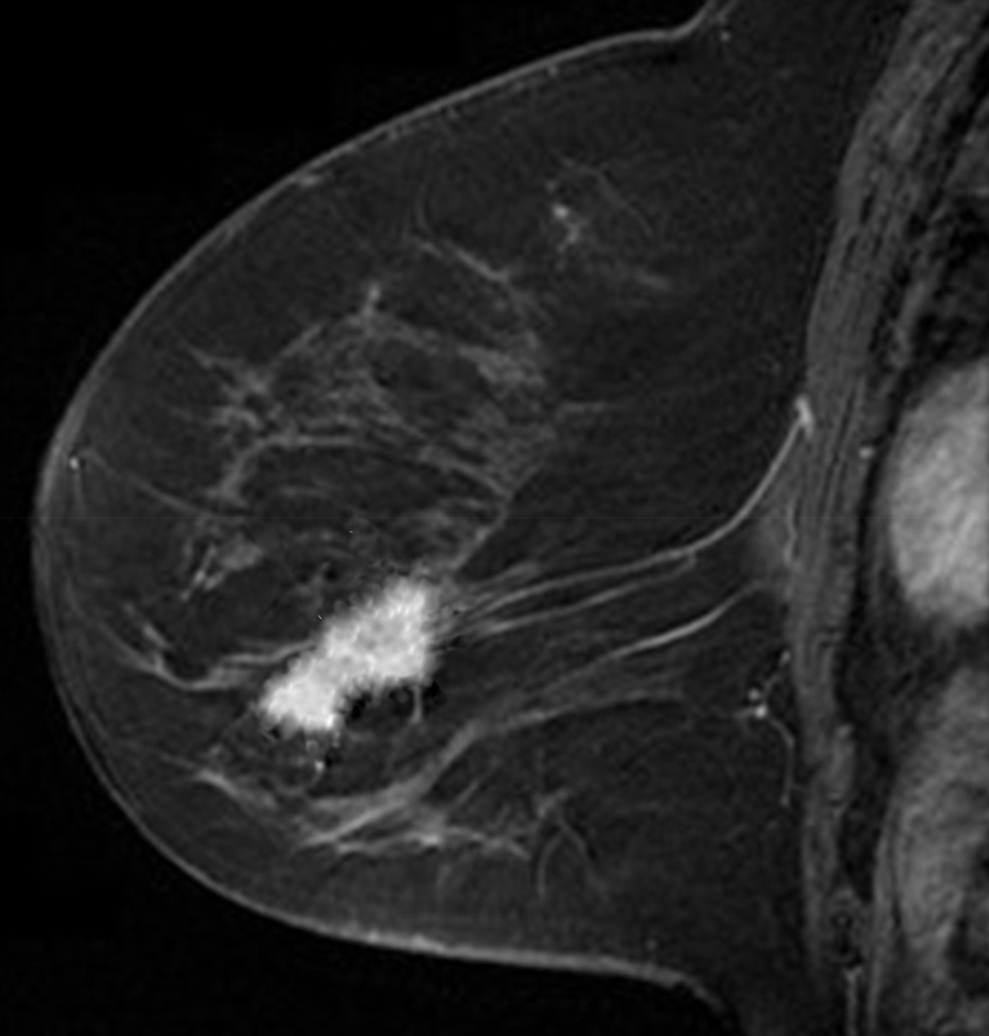

First we will use a Magnetic Resonance (MR) image of a female breast, taken from eby2008magnetic with permission from111www.slicer.org, to segment the tumor mass. On the top/right of Fig. 4, we see the first eigenfunction segmenting the tumor perfectly out of the breast image. Next, in the middle row of Fig. 4, we add to the image , of standard Gaussian noise, such that

| (15) |

where is i.i.d. Gaussian random variable with mean zero, variance equal to one and represents the noise level. Now, we compute the adaptive eigenspace of . Again, the first eigenfunction holds a nice segmentation of the tumor despite the additional noise. To demonstrate the quality of our approach, we consider the image but this time we destroy the boundaries of the tumor and change them by blurring (using an image manipulation program). The resulting image is shown on the bottom left of Fig. 4. On the bottom right of Fig. 4, we see the segmentation is accurate and captures the tumor and its blurred boundaries.

To reduce computational cost and get even more accurate results, we may create a Finite Element (FE) grid on the area of interest rather than on the image boundaries. For illustration, we consider the MR-images and shown on the top/left and bottom/left of Fig. 4, respectively. We automatically produce a mesh on the breast boundaries (see on the left of Fig. 5). The segmentation for and for is shown on the center and right of Fig. 5, respectively.